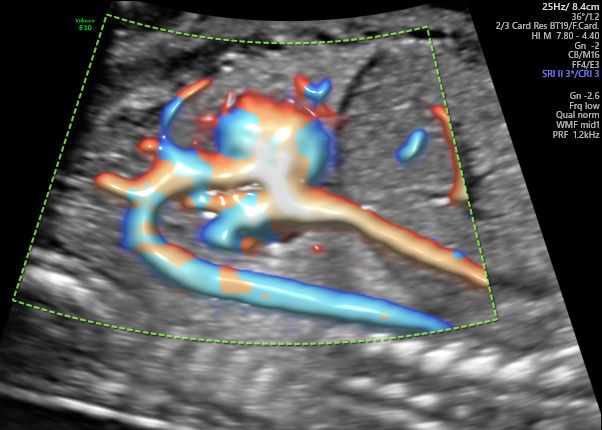

Radiantflow™

Radiantflow offre una migliore rappresentazione e una netta separazione dei vasi fornendo una maggiore percezione della dinamicità laminare del flusso sanguigno in 2D. Aggiunge informazioni di profondità e un aspetto tridimensionale e, grazie ai minori artefatti da movimento e ad una migliore definizione dei bordi, permette di identificare più facilmente e rapidamente anche i vasi più piccoli.

Radiantflow è disponibile in tutte le Modalità Color e può essere utilizzato anche in combinazione con Spettro Doppler e Color M-mode.